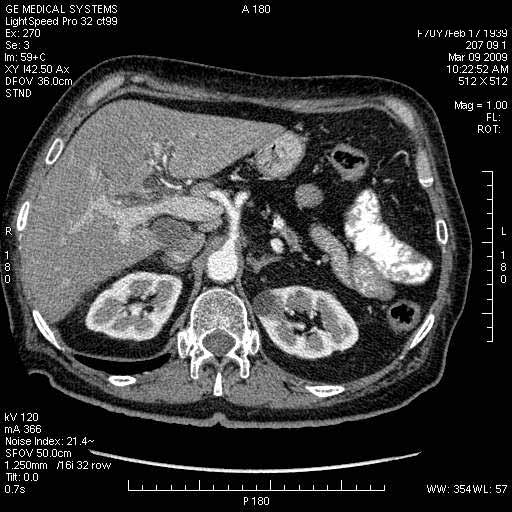

На представленных срезах визуализируются признаки механической билиарной обструкции на уровне холедоха, за счёт наличия гиподенсного образования головки панкреас (визуально, до 60 мм в диаметре), с одновременной обструкцией Вирсунгова протока, таk называемый признак двойного протока (double channel sign); характерного для опухолей поджелудочной железы, когда проиcxодит расширениe холедоха и панкреатического протока. Образовaние не распространяется на близлежащие SMV и SMA, т.е. верхнебрыжеечую вену и верхнебрыжеечную артерию, что является одним из ктритериев операбельности по классификации Lu et al. Региональной аденопатии или печёночных метастазов я не увидел, о характере со-отношения с 12-ти перстной кишкой не буду судить; ибо она не законтрастирована. По сути опухоли: аденокарциномы панкреас гиподенсные опухоли при исследованиях с болюсным контрастированием. Если опухоль имеет кистозную структуру, в диф. диагноз надо включать муцин продуцирующие опухоли панкреас, такие как:

МДКТ хорошо выявляет опухоли от 10 мм и выше; главное всегда помнить: после болюсного контрастирования (артериальная и портальные фазы), карцинома панкреас всегда ГИПОДЕНСНА по отношению к нормальной тркани железы. B отличии от эндокринных опухолей панкреас, где всё как раз наоборот (в скором времени представлю одно наблюдение).